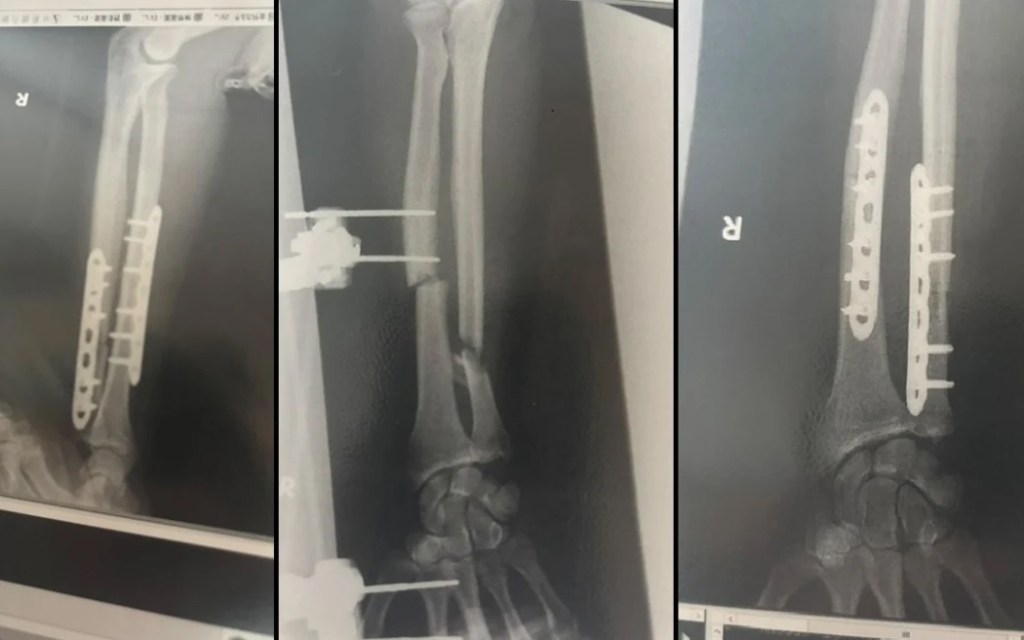

三次手術終接回 坦言沒勇氣去看手臂

在經歷三次手術後,醫生最後成功接回他的手臂。他坦承到現在還沒有勇氣去看自己的手臂,預料會留下嚴重疤痕,但不會阻止他繼續去山區跑步。他又感謝許多人在他康復期間給予支持與鼓勵。